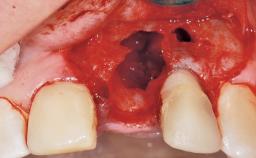

A 39-year-old male patient presented with a chief complaint of discomfort and gingival discoloration around his maxillary left central incisor. He was in good general health and was a non-smoker. His past dental history was significant because of the traumatic fracture of tooth 21 in a sporting accident at age 13. Initial dental treatment included endodontic therapy and a full-coverage restoration. The patient became symptomatic 5 years later, when structural failure of the tooth resulted in the dislodgment of the crown. Endodontic retreatment, apical surgery, and post-and-core restoration were performed.

Bone Augmentation Horizontal|Staged

Augmentation Materials Xenogenous|Membrane

Bone Volume Deficient horizontally, requiring prior grafting